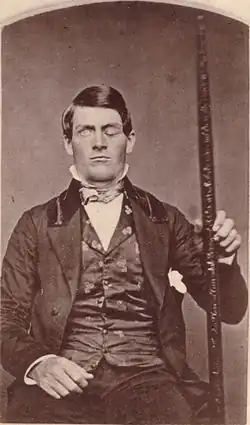

Финеас П. Гейдж (англ. Phineas P. Gage; 9 июля 1823 — 21 мая 1860 года) — американский строитель, получивший тяжёлое ранение головного мозга при прокладке железной дороги.

Доктор Джон Мартин Харлоу, который знал Гейджа до его несчастного случая, охарактеризовал его как «полностью здорового, сильного и энергичного двадцатипятилетнего молодого человека, нервно-желчного типа, ростом пять футов шесть дюймов [168 см], с весом около ста пятидесяти фунтов [68 кг], обладающего стойким характером и крепким телосложением; его мускулатура была невероятно развита — он почти никогда не болел с детства до получения травмы». В то время, когда френология теряла популярность, нервно-желчный темперамент означал особое сочетание «возбудимых умственных сил» с «энергией и силу разума и тела», позволяющее выдерживать значительные умственные и физические нагрузки.